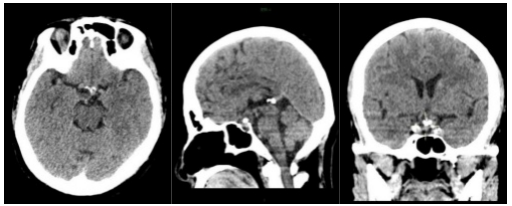

②磨除鞍底 暴露蝶窦前壁,磨钻磨除蝶窦前壁,确定鞍底后磨钻磨开鞍底骨质,上至蝶骨平台,下至斜坡,双侧至颈内动脉隆起,骨窗大小约2.5cm×2.5cm,鞍底骨窗周围骨质充分磨平,显露硬脑膜。

③分离切除肿瘤 术中切开硬脑,见肿瘤位于鞍上,内可一囊性病变,起源于垂体炳,可见机油样内容物,血供一般,有钙化斑,内镜下仔细分离肿瘤包膜、垂体上动脉及周围穿支血管等,切开肿瘤内减压后,将钙化灶、内容物及肿瘤分块切除,肿瘤切除后可见垂体上动脉、基底动脉、后交通动脉等血管保护完好,视交叉及供血血管无损伤,垂体柄结构完整。

④鞍底重建修补 术中高流量脑脊液瘘,鞍底重建预防术后脑脊液鼻漏,避免颅内感染,术中采用多种组织修补鞍底,使用人工硬膜内嵌至硬脑膜切缘周边,取大腿部脂肪、肌肉筋膜及鼻中隔粘膜瓣重建修补鞍底,明胶海绵填塞,最后使用碘仿纱条填塞双侧鼻腔进一步支撑并压迫止血。

⑤术后复查 肿瘤全部切除,术区无渗血。

本患者肿瘤位于鞍内及鞍上区域,呈囊实性,与下丘脑粘连紧密,伴钙化明显,视神经、垂体柄受压移位明显,毗邻重要神经血管结构,手术难度较高,术中早期瘤体中心减压可以为肿瘤的包膜外分离提供空间,尤其是一些囊性成分的减压。对蛛网膜平面进行锐性和轻柔的分离是非常重要的,可以避免供应视交叉的垂体上动脉分支血管的损伤。术中选用成角内镜可以进一步观察和切除直视下难以到达的角落里的残余肿瘤。术前通过影像学表现判断垂体柄的位置,术中根据垂体柄与肿瘤的关系,尽可能多地或完整地保留垂体柄,可减轻术后尿崩症的发生率。本患者术中视神经、垂体柄、穿支血管保护完好,肿瘤完全切除,术后患者视力下降、乏力等症状明显改善,无垂体功能低下、脑脊液鼻漏、颅内感染等并发症,患者生活质量得到很大改善,患者家属满意度较高。目前,经鼻蝶微创手术成为颅咽管瘤的主要手术方式,减少手术创伤,缩短手术时间及住院时间,也为患者降低了经济负担。